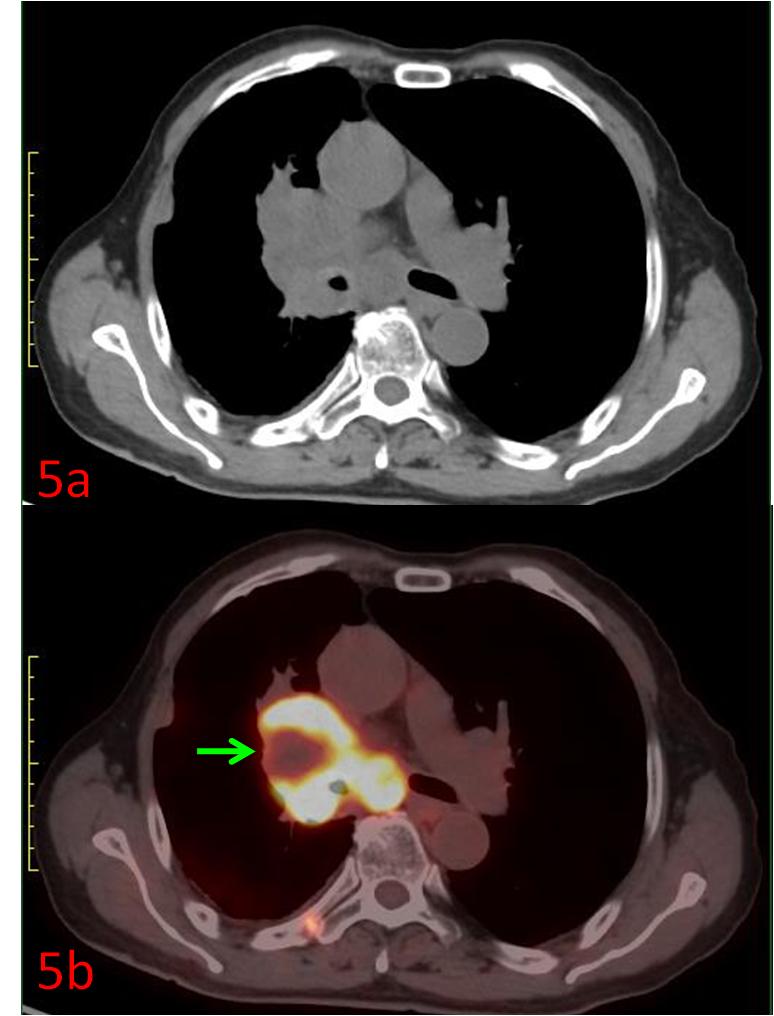

例5:中年女性,右肺上葉小細胞癌,CT示右肺門腫塊(圖5a),PET/CT展示了腫瘤內部代謝的不均質,中心區域存在部分壞死組織(圖5b綠箭),為放療計劃制定提供更準確信息。